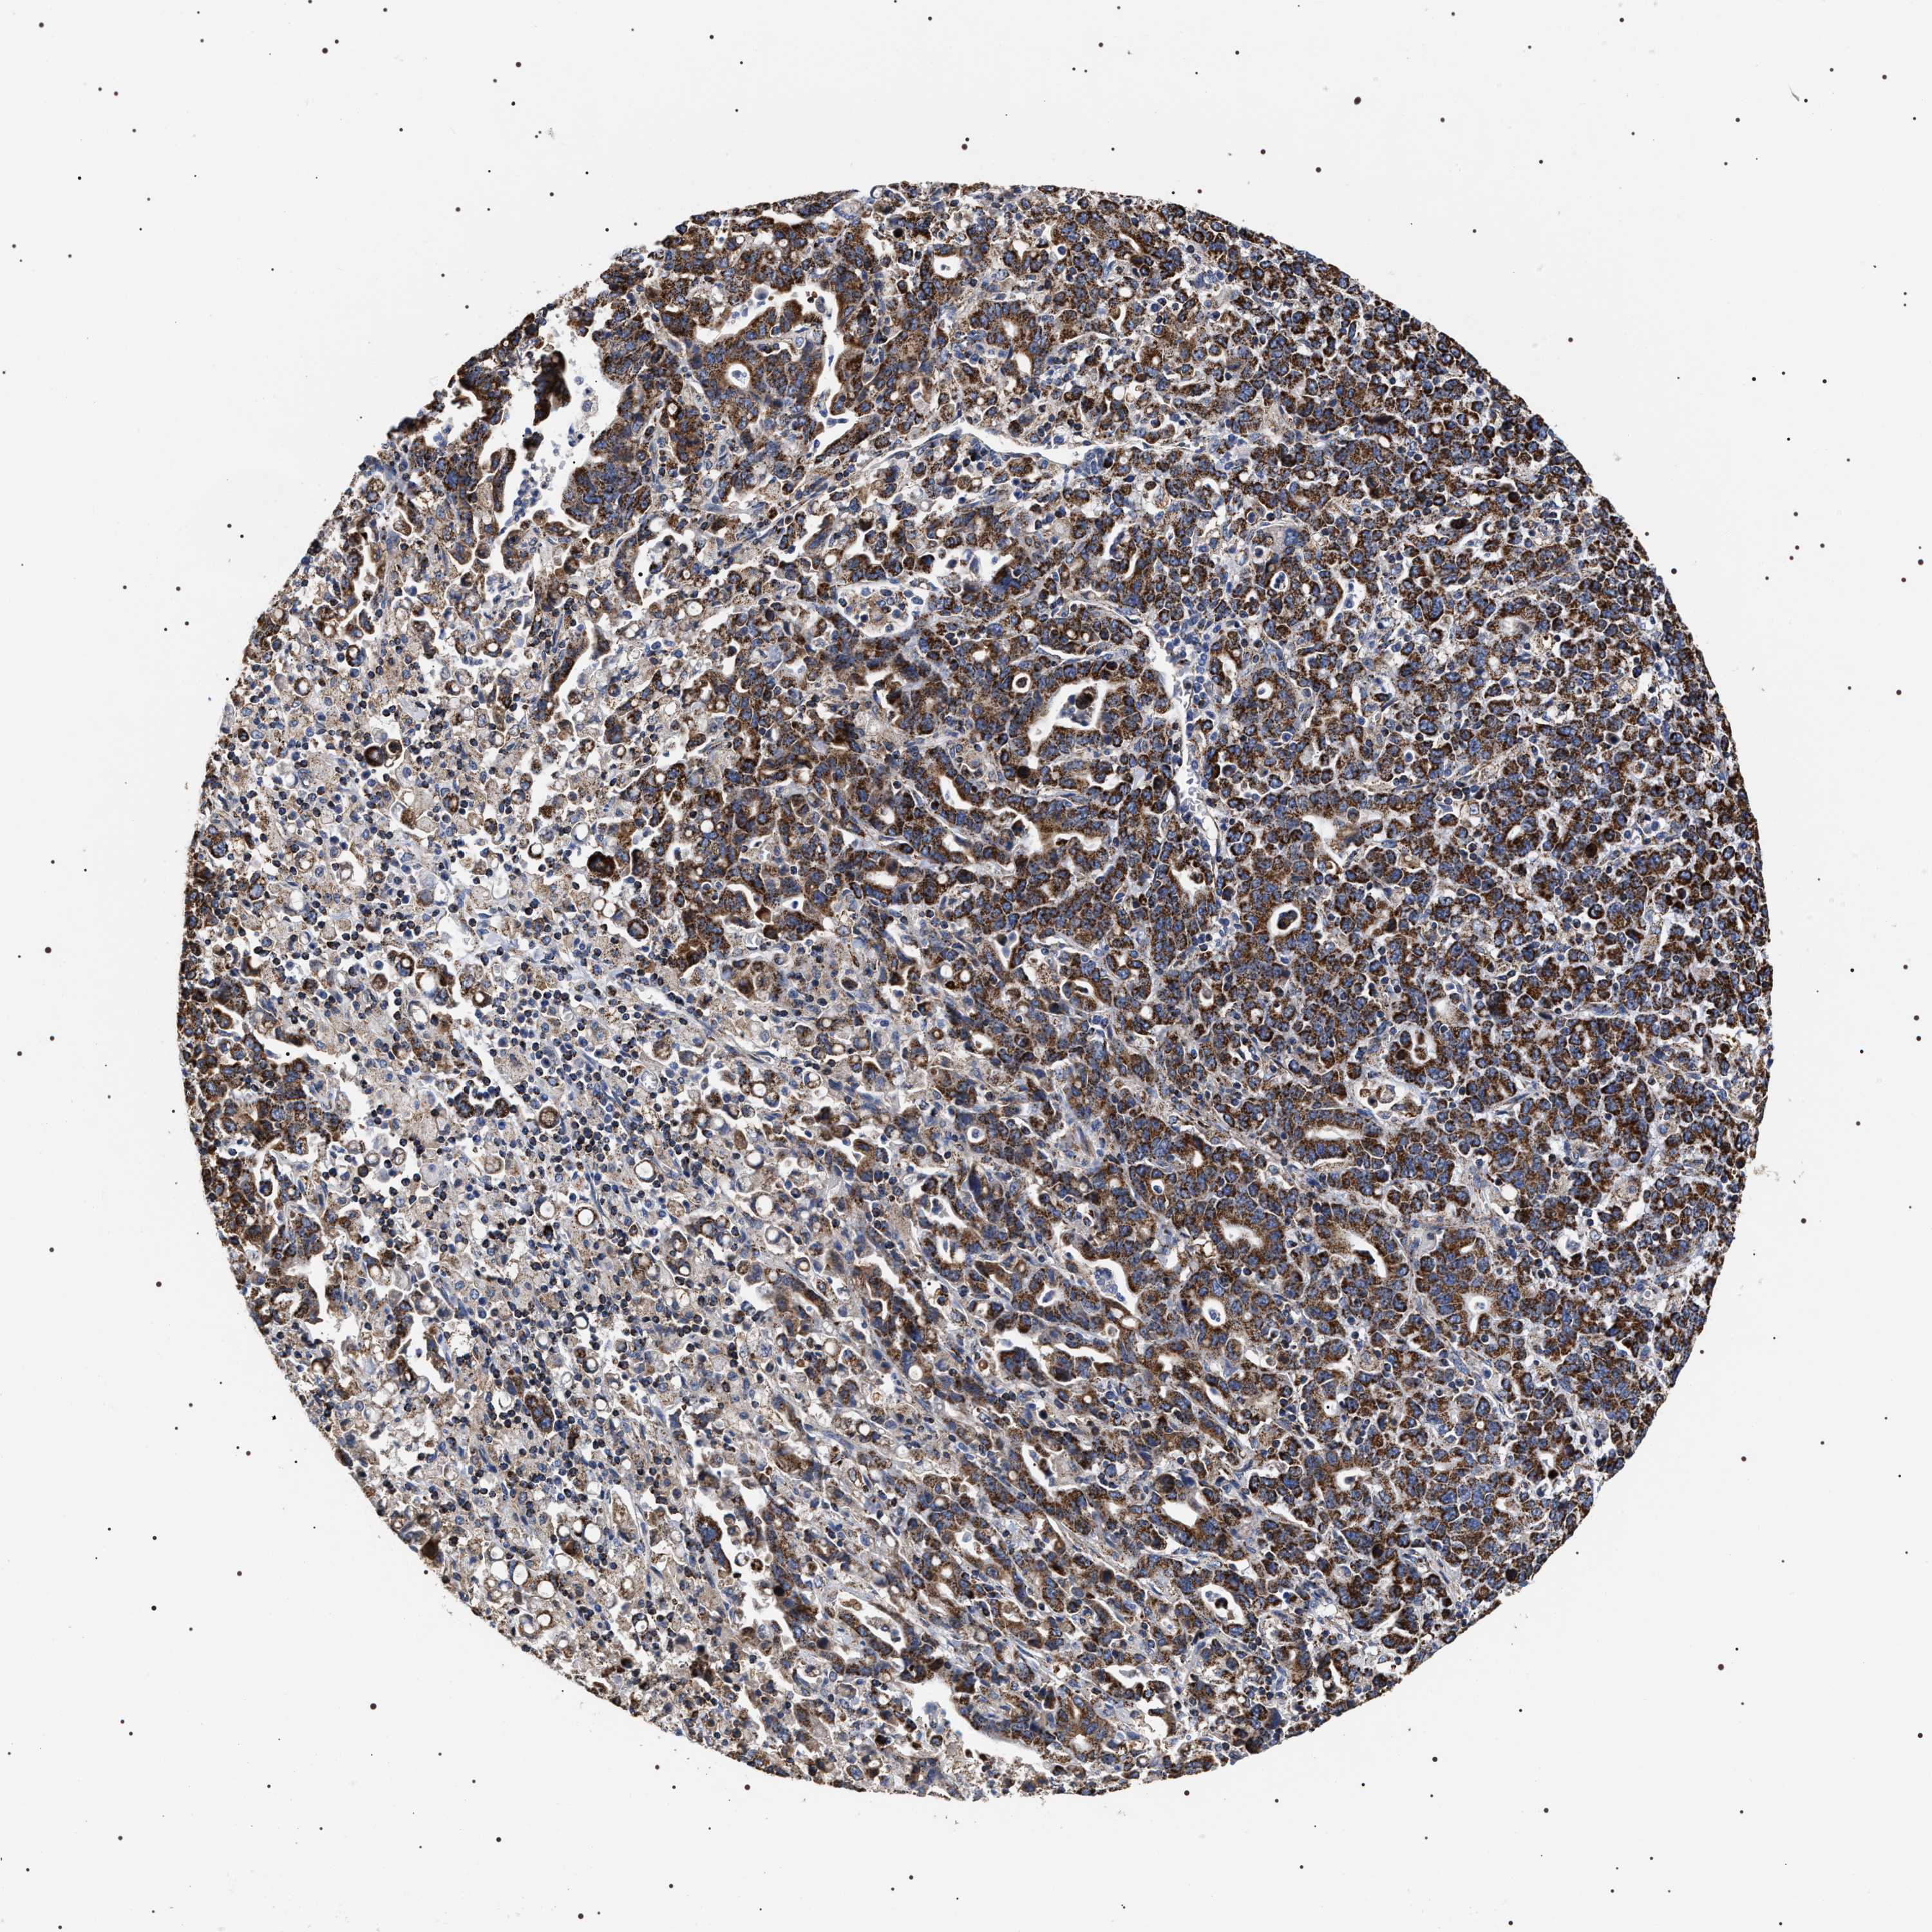

STOMACH CANCER - Protein expressioni

A mouse-over function shows sample information and annotation data. Click on an image to view it in a full screen mode. Samples can be filtered based on level of antibody staining by selecting one or several of the following categories: high, medium, low and not detected. The assay and annotation is described here.

Note that samples used for immunohistochemistry by the Human Protein Atlas do not correspond to samples in the TCGA dataset.

Antibody stainingi

Antibody staining in the annotated cell types in the current human tissue is reported as not detected, low, medium, or high, based on conventional immunohistochemistry profiling in selected tissues. This score is based on the combination of the staining intensity and fraction of stained cells.

Each image is clickable and will lead to virtual microscopy that enables deeper exploration of all samples and also displays staining intensity scores, fraction scores and subcellular localization as well as patient and tissue information for each sample.

Antibody HPA020300

Staining

High

Medium

Low

Not detected

Intensity

Strong

Moderate

Weak

Negative

Quantity

>75%

75%-25%

<25%

None

Location

Nuclear

Cytoplasmic/membranous

Cytoplasmic/membranous,nuclear

Adenocarcinoma, NOS